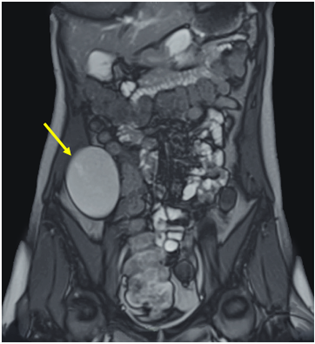

Se realizó ecografía abdominal visualizándose masa hipoecogénica en fosa ilíaca derecha, de contornos bien definidos, inmediatamente anterior al músculo psoas derecho. En la tomografía computarizada (Figura 1) y en la resonancia magnética (Figura 2) de abdomen se observó una lesión de densidad quística, de localización aparentemente extracompartimental en íntima relación con músculo transverso del abdomen derecho, que desplazaba el colon ascendente.